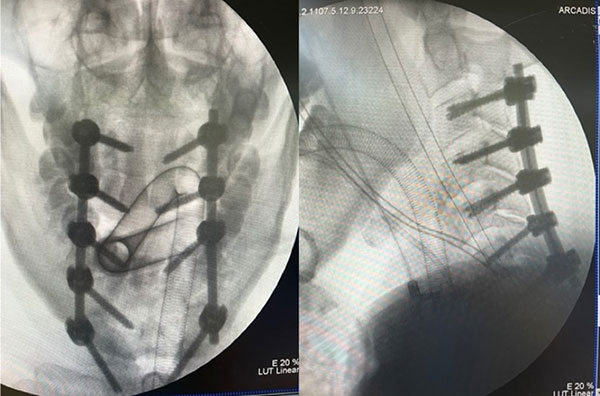

考虑到患者四肢瘫痪且颈6弓根骨折,脊柱外科昌耘冰主任及郑晓青副主任医师认为椎弓根螺钉固定能起到稳定骨折、坚强固定且为以后患者的生活质量提供必要支持。手术过程并非一帆风顺,因为患者创伤应激及心功能不全等问题,一度出现血压波动及房颤、室上速心率失常等情况。医务人员以高超的技术、沉着的心态、冷静的职业素养应对着一个又一个难题,完成手术后送至重症医学科密切监护。